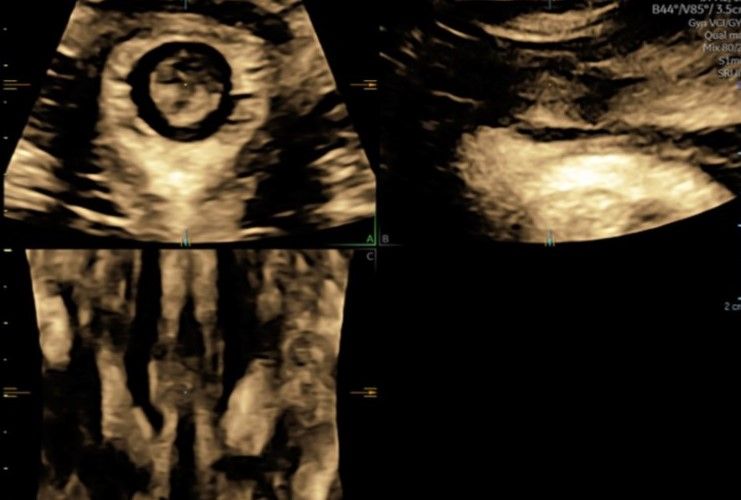

Eseguo in particolare ecografie ostetriche e ginecologiche anche in 3D e 4D per meglio identificare la problematica, offrire diagnosi precise ed un trattamento mirato e personalizzato.